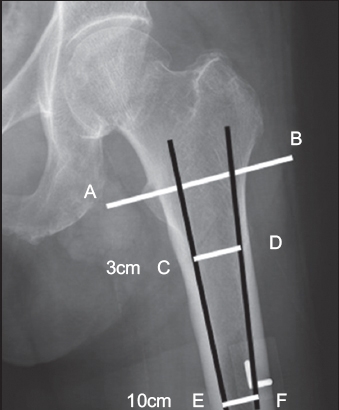

Proximal femur morphology was analysed using the canal-to-calcar isthmus ratio, as described by Dorr et al.(8) Measurements were made based on AP radiographs of the hip contralateral to the femur neck fracture. A horizontal reference line was drawn from the apex of the lesser trochanter. Two points on the endosteal margins of the femur (3 cm and 10 cm below the reference line) were identified. Lines joining the distal and proximal endosteal points were drawn on the lateral and medial sides. The two longitudinal lines intercepted the mid-lesser trochanteric line at two points; the distance between these two points was the proximal calcar isthmus diameter. The horizontal distance between the two endosteal margins, at 10 cm below the reference line, was the canal diameter. The CC ratio was obtained by dividing the canal diameter by the calcar diameter. The method of measurement is shown in

Fig. 1

Anteroposterior radiograph of the hip shows the measurement method. The calcar-to-canal width ratio is obtained by dividing the canal diameter (line EF) by the calcar diameter (line CD). These two diameters are 3 cm and 10 cm, respectively, below reference line AB, which goes across the apex of the lesser trochanter. The two black lines join C and E as well as D and F along the endosteal margins.